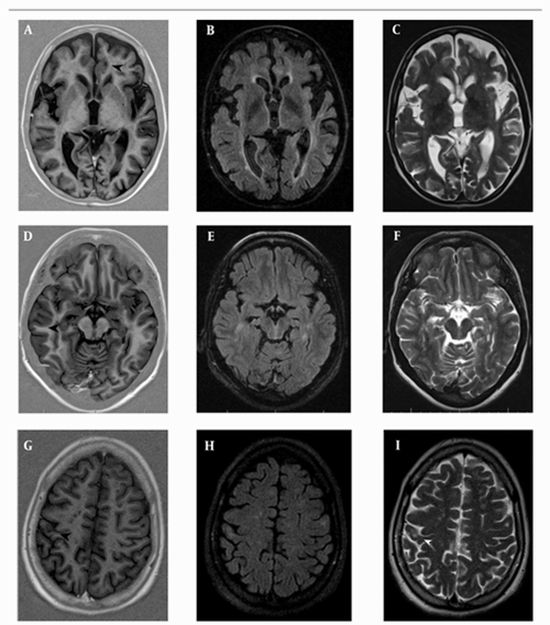

Comparison of Phase Sensitive Inversion Recovery and Conventional Magnetic Resonance Imaging for Detection of Cortical Plaques in MS Patients